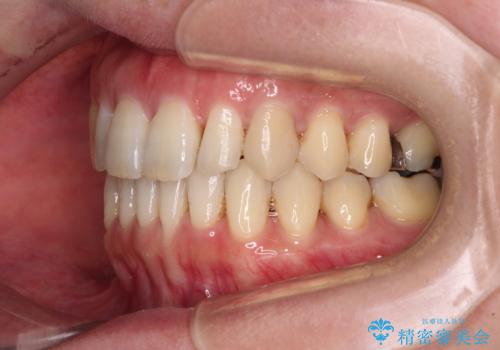

八重歯のインビザライン矯正治療

- 下顎の八重歯と、上下のクロスバイトを気にして来院された患者様です。

インビザラインを用い、下顎全体の後方移動、IPR(歯と歯の間を削る)と歯列全体を拡大させることで、歯並びを整えていくこととしました。

奥に位置していた上の前歯が下の前歯を乗り越える際、奥歯でものを咬むことができず、辛い時期が続きました。